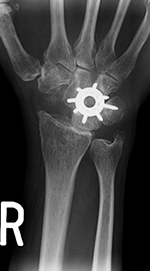

Total or partial wrist fusion is sometimes performed for severe carpal osteoarthritis. In this regard, a spider plate may be used for partial carpal arthrodesis (figure: spider plate). Modular plate systems are available for four-corner and other limited wrist fusions for osteoarthritis, complex fractures, revision of failed previous wrist fusions, marked carpal instability, or rheumatoid arthritis (figure: Acumed hub cap fusion plates).

Spider plate for partial wrist arthrodesis |

|

The scaphoid has been removed. The spider plate transfixes the lunate, triquetrum, capitate, and hamate which are partially fused. From Taljanovic, 2005 |